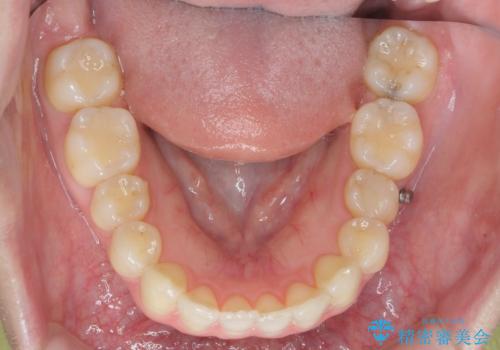

カリエール・マイクロインプラントを併用した歯の突出を改善する大きな遠心移動

- 口が閉じづらく、突出し歯が出っ歯に見えてしまうことの改善を求めて来院されました。

通常このような場合、抜歯してのワイヤー矯正治療も選択肢に入りますが、患者様の強い希望により抜歯を行わずマウスピースによる治療を選択しました。

カリエール・マイクロインプラントを用い、時間はかかりましたが大きく歯の後方移動が達成され、前歯の見た目が大きく改善されました。

大きな後方移動を達成するにはマイクロインプラントと日常的なゴムかけが大切です。